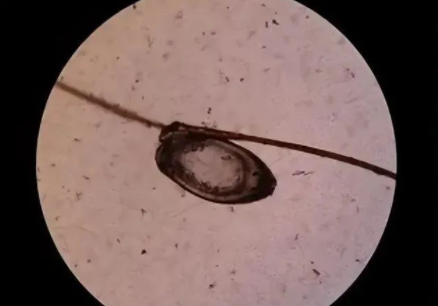

阴虱的体型扁平,外形看起来就好像一只小螃蟹,阴虱依靠吸人体的血液为生,每天能够吸血4~5次,阴虱在吸食前身体是灰白色的,在吸食后会变为铁锈色。